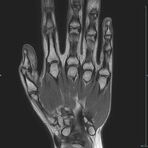

Gelenke

Hand

• Beurteilung von Knochen, Bändern und anderen Weichteilstrukturen der Gelenke nach Unfall.

• Arthrosediagnostik (Knorpelschaden)

• Impingement-Symptomatik

• Ursachenklärung bei wiederholter spontaner Gelenkluxation

• Ausbreitungsdiagnostik bei Gelenkentzündung, z.B. im Rahmen von rheumatischen Grunderkrankungen

Arthrographie

• MR-Arthrographie – nach örtlicher Betäubung und gründlicher Desinfektion der Haut wird unter Lagekontrolle mit Röntgen-Durchleuchtung eine kleine Nadel in den Gelenkraum positoniert und darüber ein MR-taugliches Kontrastmittel in den Gelenkraum gespritzt. Danach wird die Nadel entfernt. Anschließend erfolgt die MRT des Gelenkes. Diese Methode stellt kleine anatomische Strukturen des Gelenkraumes verbessert dar, z.B. zur Therapieplanung vor Arthroskopie bei Sportverletzungen der Schulter oder Gelenkinstabilität.